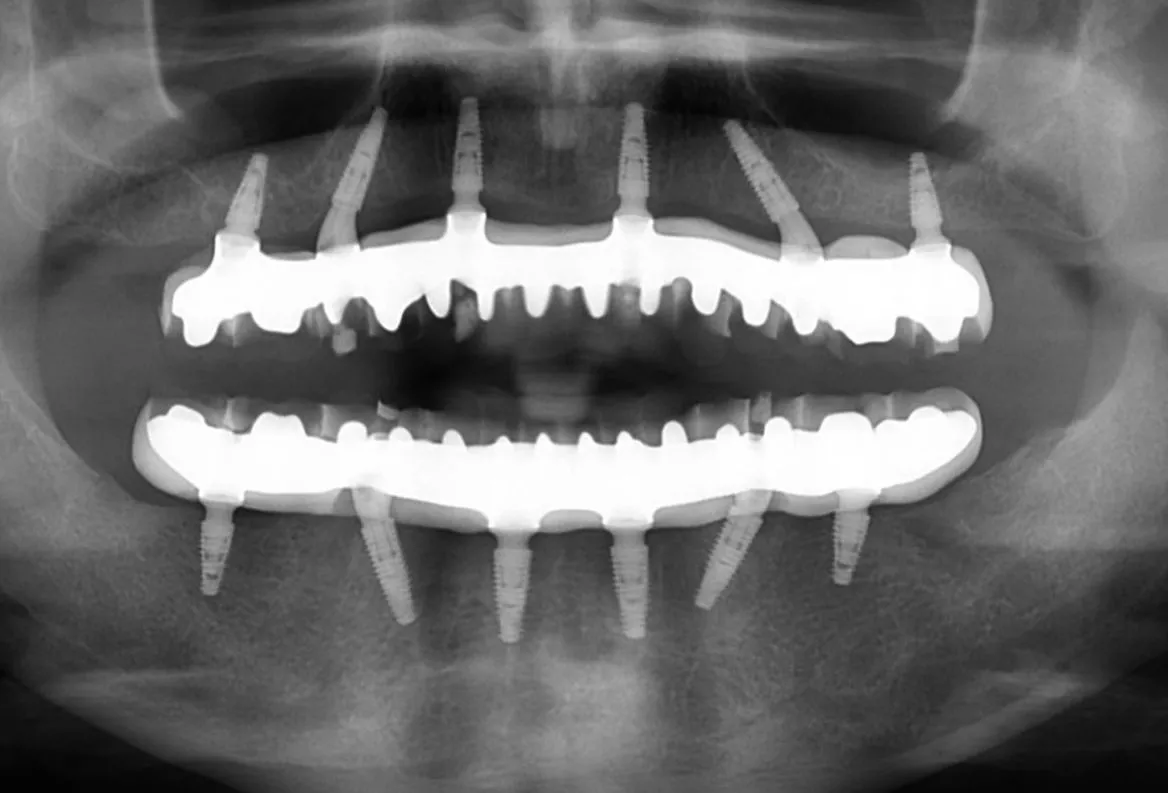

5. Smile-in-a-day dental implants (also known as all-on-4, same day smile, and full jaw dental implants): These long-lasting dental implants provide a comprehensive solution for replacing loose, decayed, and missing teeth. In just one day, these implants are placed into the jaw, offering a full set of functional teeth.

The smile-in-a-day procedure offers a lasting solution for individuals dealing with issues such as dentures, loose or decayed teeth, as well as missing or failing teeth. In just one day, our skilled & friendly team can provide you with a complete set of dental implants, transforming your smile and restoring your oral health.

Our dental implant treatment is focused on restoring our patients’ smiles to a healthy and functional state. We prioritize long-term solutions and do not offer temporary dentures. Instead, we create a custom-designed, milled, and screw-retained prosthetic specifically tailored to each individual.

Thanks to our exceptional clinic setup and in-house laboratories, we can complete the entire treatment process in a single day. This means that you can leave our clinic with a brand new “smile-in-a-day,” having received the comprehensive treatment, prosthetic design, and fitting all within the same day.

Shortly after settling in, any remaining teeth will be extracted, and the dental implants will be placed. This procedure is performed under local anesthesia and sedation is also available as an option (that will be discussed with you beforehand). We will also conduct bite calculations and take impressions. Your personalised prosthesis will be manufactured on the same day while you relax in your private patient suite.

Later in the day, your smile-in-a-day dental implants will be placed. These implants will remain in your mouth for a few weeks, allowing time for proper integration and healing. You will then return to the clinic for the final fitting of your prosthesis, ensuring an optimal result and a comfortable fit.